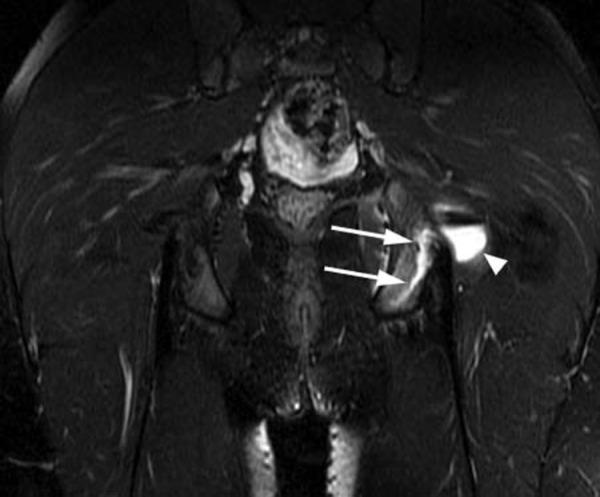

Orthopaedic magnetic resonance imaging challenge: apophyseal avulsions at the pelvis.

Apophyseal avulsion injuries of the hip and pelvis are frequent athletic injuries in children and adolescents, most commonly associated with explosive movement or sprinting. This article details typically encountered apophyseal injuries and their appearance on magnetic resonance imaging.